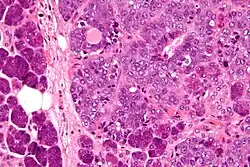

| Micrograph of an epithelial-myoepithelial carcinoma (right of image). The epithelial component has a tubular morphology and is evident only focally (upper left of image). Benign serous glands (parotid salivary gland) are also seen (left of image). H&E stain. | |

This tumour is characterised by biphasic tubular structures composed of inner ductal and outer clear myoepithelial cells.

The histologic differential diagnosis includes adenoid cystic carcinoma and pleomorphic adenoma.